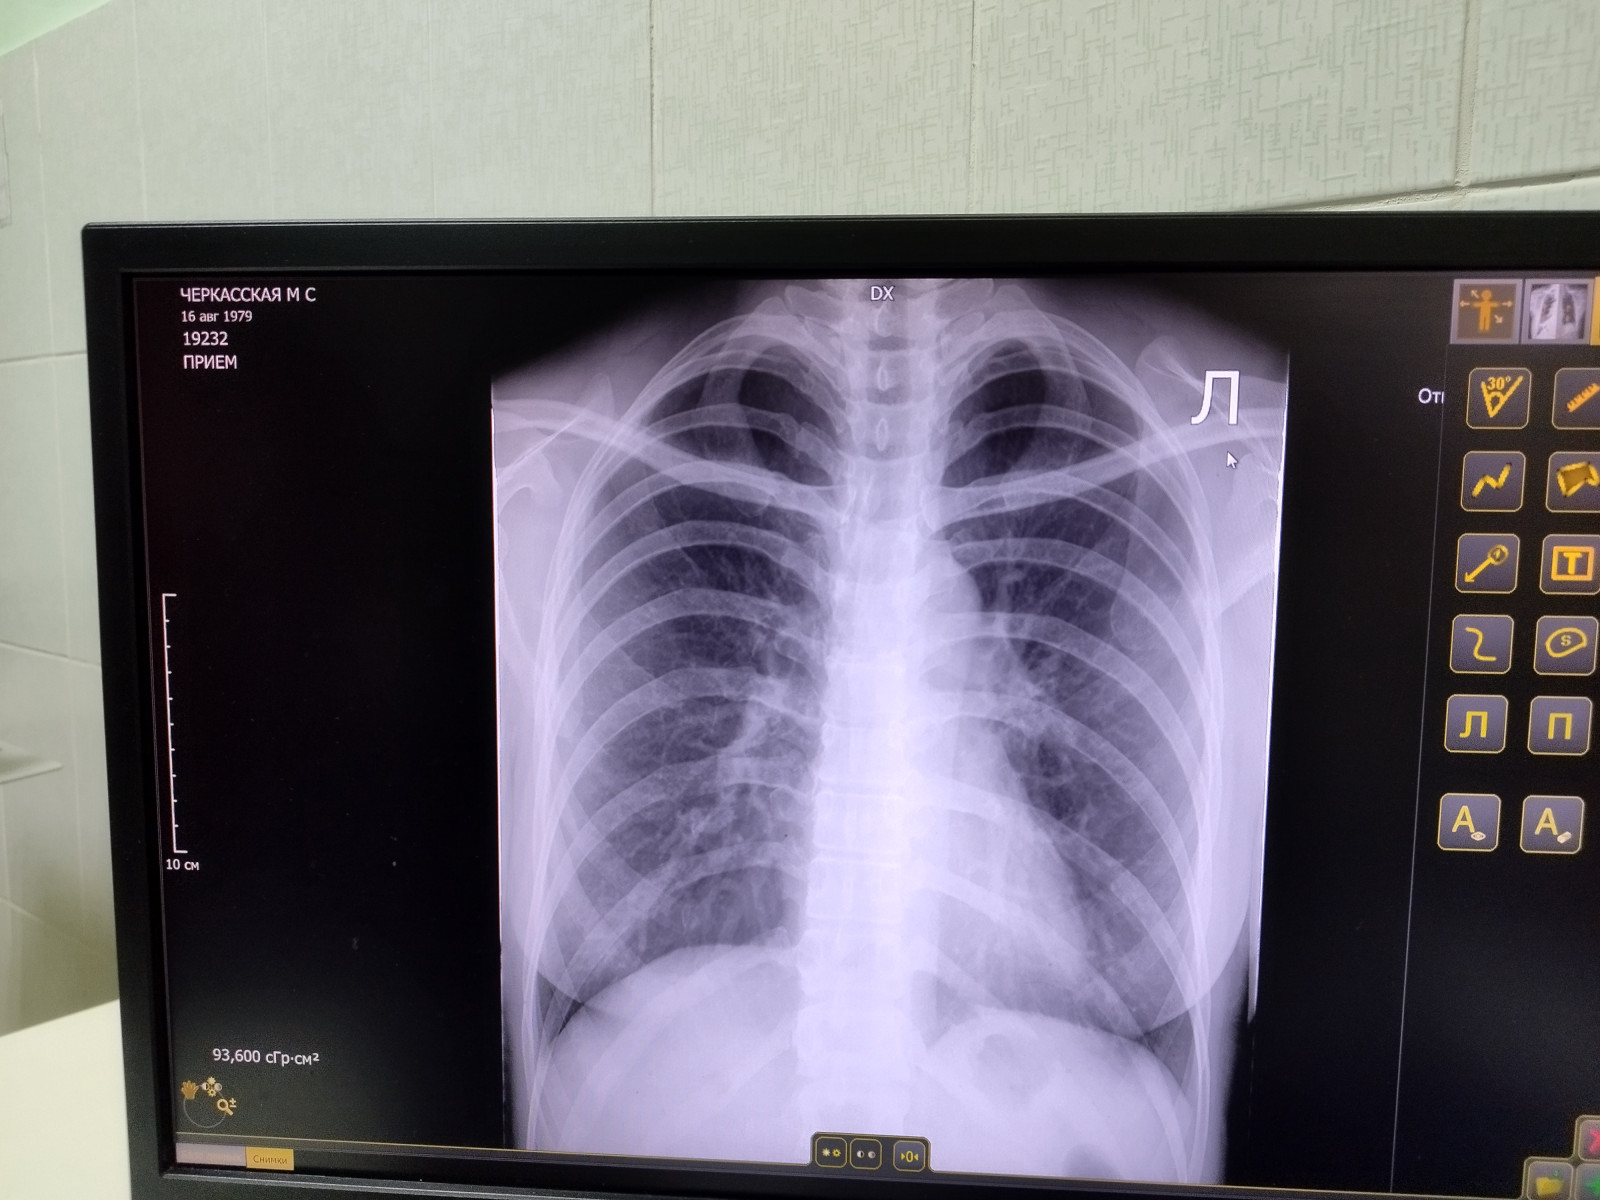

Какой антибиотик пить при определении очаговой инфильтрации в легочном поле слева?